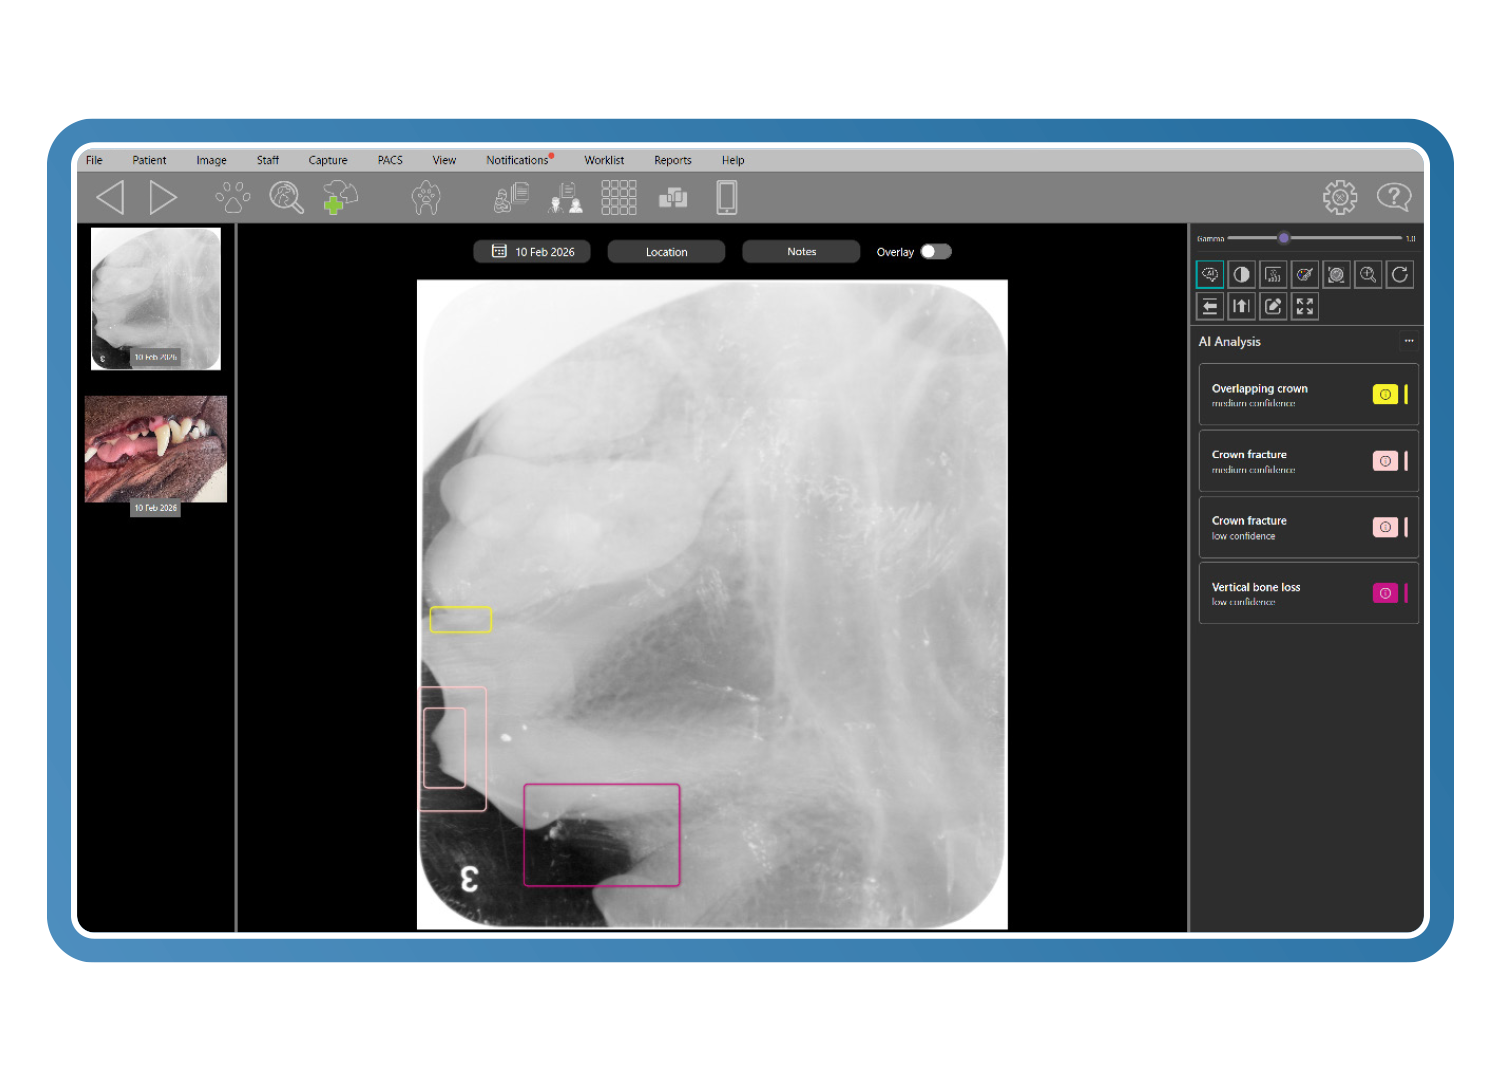

Optimización Clarity y reconocimiento de patologías (más de 70 afecciones)

Clarity identifica más de 70 patologías dentales y orales utilizando datos fotográficos y radiográficos. Entrenado con casos revisados por pares de odontólogos veterinarios certificados por el consejo, resalta anomalías en menos de 0,5 segundos, apoyando - sin sustituir - el diagnóstico clínico y acelerando una toma de decisiones segura y fundamentada.

Herramientas diagnósticas específicas para veterinaria

Las herramientas avanzadas de imagen veterinaria mejoran el detalle diagnóstico incluso a partir de imágenes subóptimas. El análisis de Clarity detecta cambios con una diferencia de contraste de tan solo un 2 %, mientras que los filtros inteligentes y la visualización en pseudocolor revelan la pérdida ósea y los detalles periodontales, reduciendo las repeticiones y convirtiendo imágenes de baja calidad en imágenes diagnósticas.